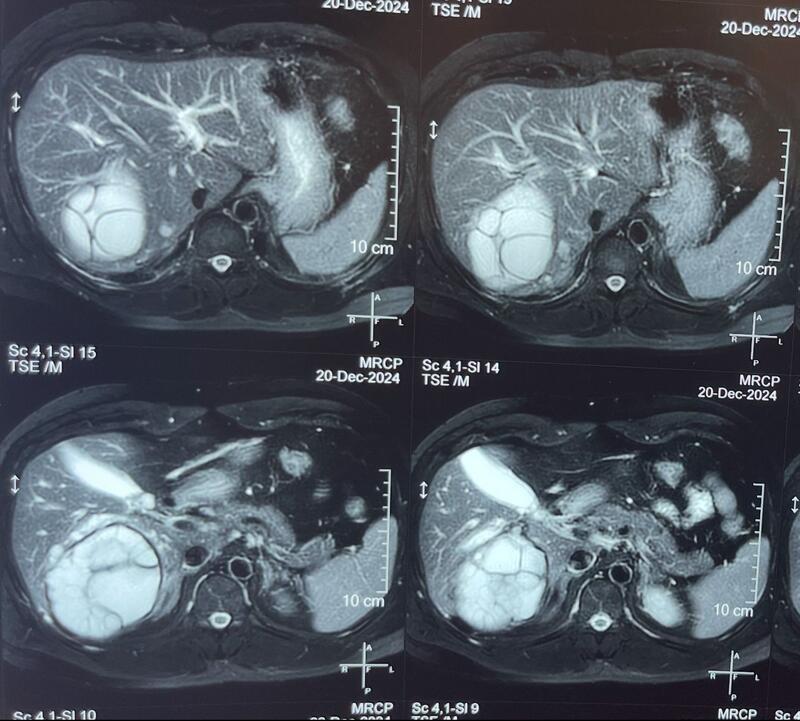

Blood investigations showed obstructive jaundice. CT Abdomen and pelvis with MRCP confirmed a large hydatid cyst in the right lobe of the liver measuring 12x14 cm, compressing the right biliary ducts (posterior ducts), with no obvious biliary communication. Associated cholecystitis with sludge in the gallbladder was also noted.